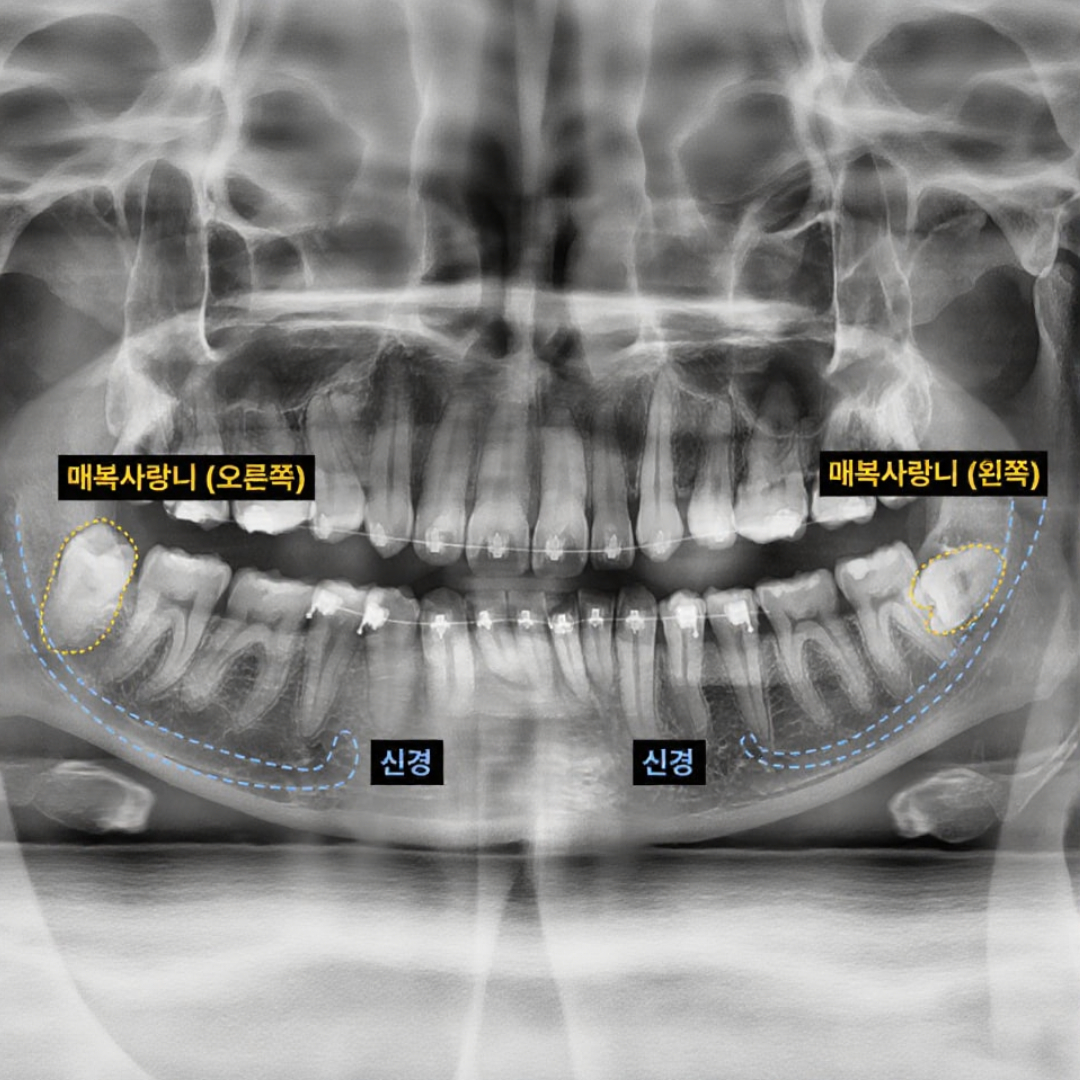

- 사랑니 발치

- 대학병원 의뢰 케이스도 문제없다. : 사랑니 발치, 이제 멀리 갈 필요 없습니다.

- 사랑니 발치

- 대학병원 의뢰 케이스도 문제없다. : 사랑니 발치, 이제 멀리 갈 필요 없습니다.